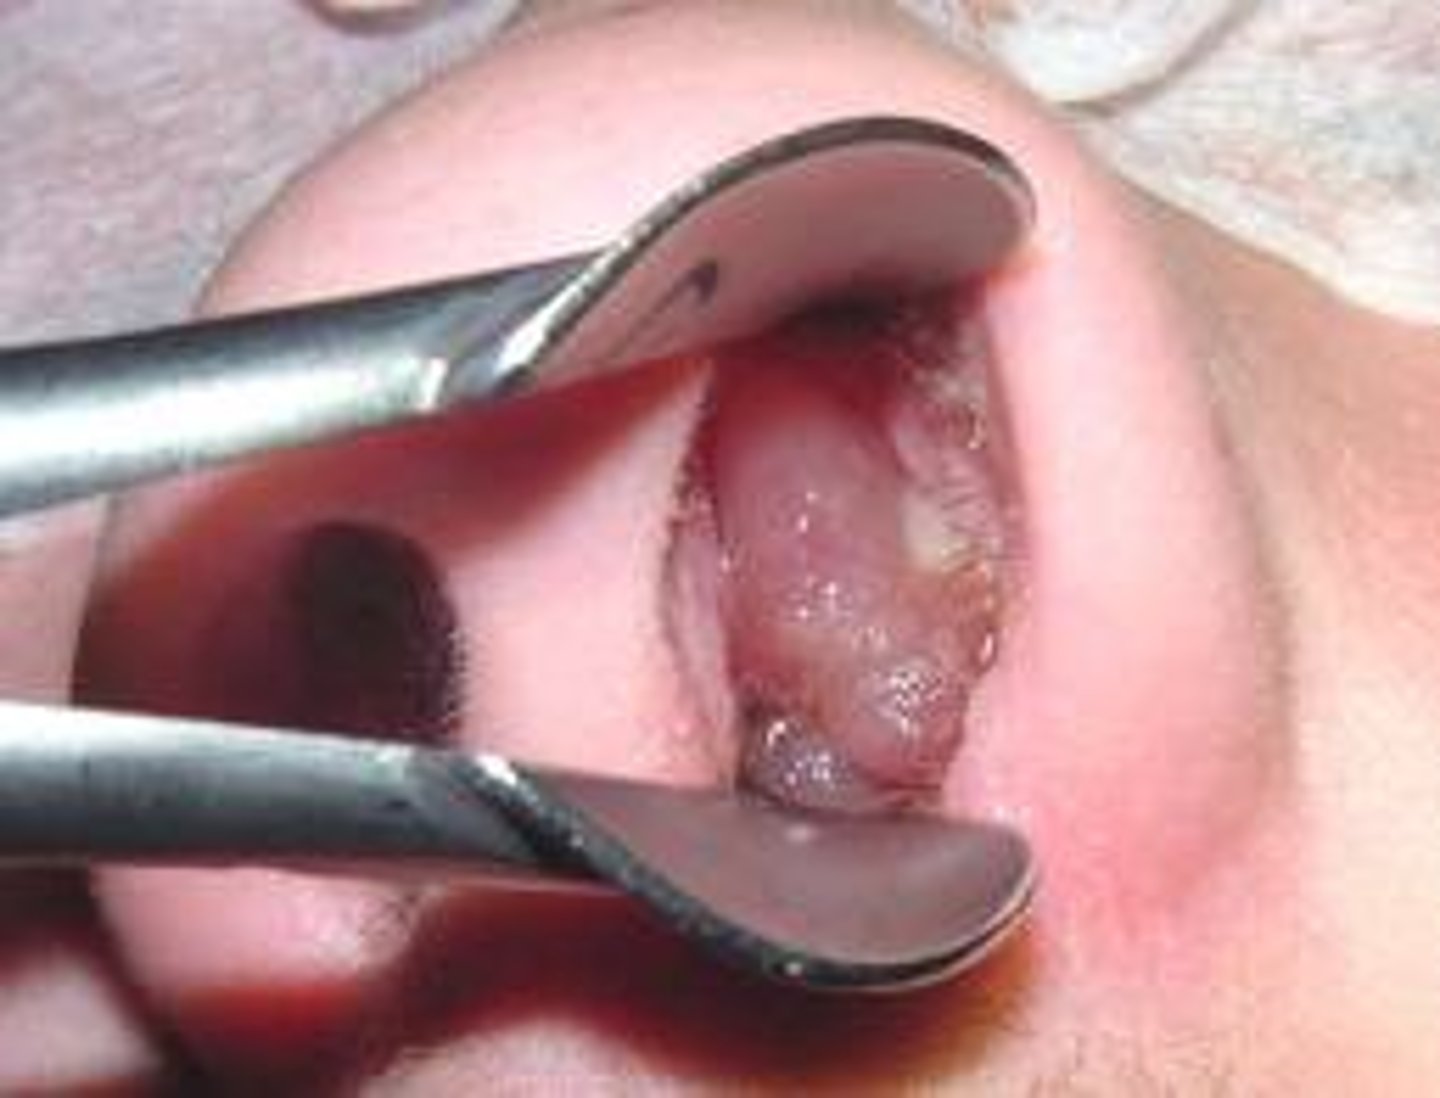

nasal polyps

<p>Benign tumors found on the nasal turbinates, originating in the maxillary and ethmoid sinuses</p>

what may patients with nasal polyps have in their history?

Nasal obstruction, hyposomia, secondary sinusitis, Samter Triad, Cystic Fibrosis

diagnosis of nasal polyps

Physical exam: pale/pearly and translucent nodule(s) of inferior turbinates

Nasal endoscopy